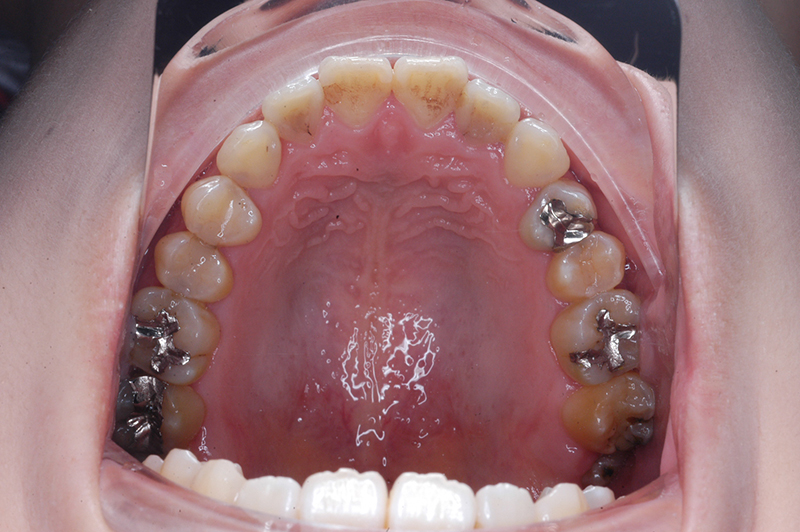

初診時

FP・IOP

主訴 受け口 診断名 アングルⅢ級反対咬合症例

口腔内所見 臼歯関係はⅢ級、下顎歯列はスピーカーブによって前歯は舌側へ倒れこみつつ挺出しておりover jet-2.5mm、over bite3.0mmと反対咬合を呈していた。